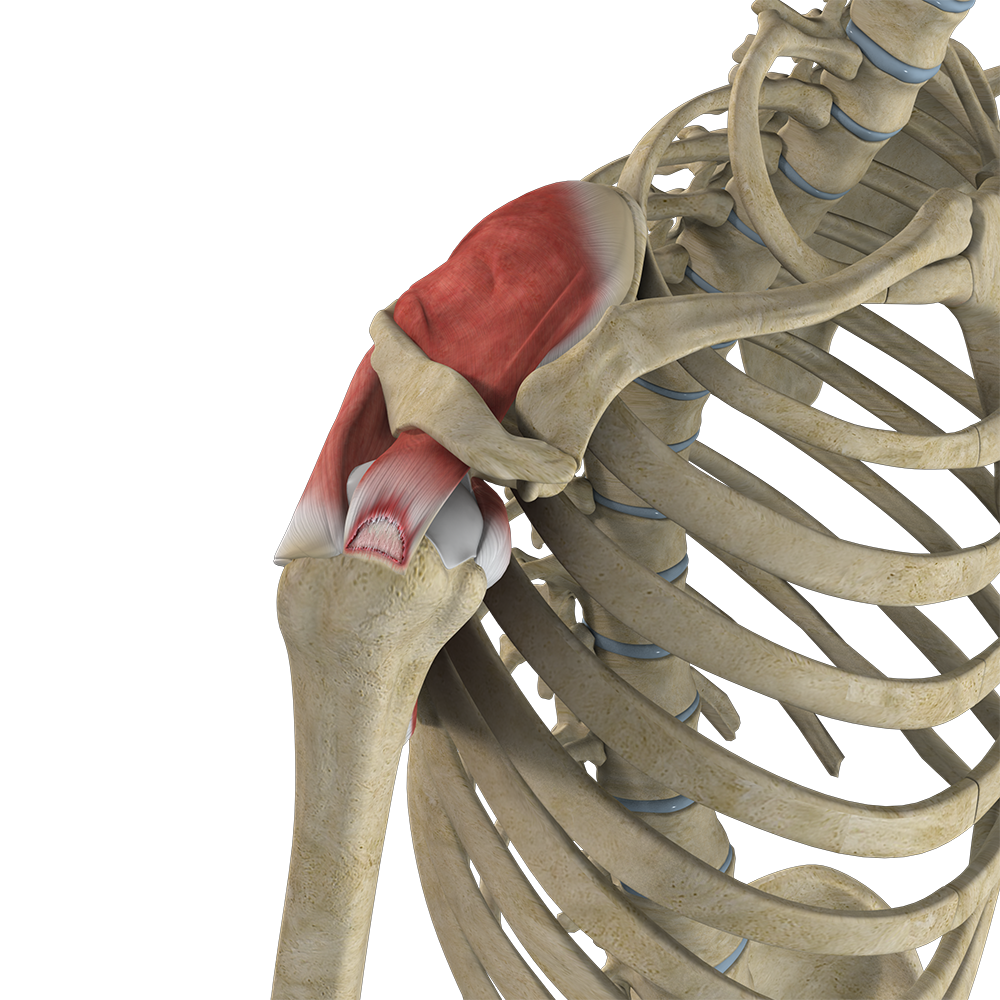

Rotator Cuff Tear

A rotator cuff tear is an injury where one or more of the tendons in the rotator cuff (the group of muscles and tendons that stabilize the shoulder and enable arm movement) become partially or completely torn.

Rotator Cuff Arthropathy

The rotator cuff consists of 4 muscles that stabilize the ball and socket joint of the shoulder during movement.

Partial Rotator Cuff Tear

A partial rotator cuff tear is an incomplete tear that involves damage to a part of the tendon.